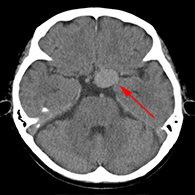

くも膜下出血の原因となる脳動脈瘤(のうどうみゃくりゅう)の外科治療

63歳女性、左眼視力低下で発症

<画像所見>

左眼の奥に大きな動脈瘤認める。

(→動脈瘤)

<手術方法>

左前頭側頭開頭で動脈瘤クリッピング術を行った。

手術中は脳血管撮影装置を用いたHybrid手術を施行し、動脈瘤の消失を手術中に確認する。

手術中MEP(運動神経)VEP(視力)モニタリングで術後の視力低下や手足の麻痺を予防する。